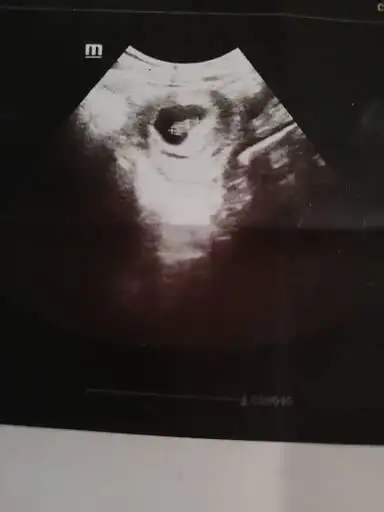

Banada yorum yaparmısınız 7+1 alttan muane ile bakıldı kalp atıslarını duydumuz gün. Hiç farketmiyor cinsiyeti ama ramzi diye bişey duydum 🤗

Eklentiler

• CCF45B50-6749-43E3-8A10-21E171D06DB2.webp

CCF45B50-6749-43E3-8A10-21E171D06DB2.webp

26,5 KB · Görüntüleme: 84